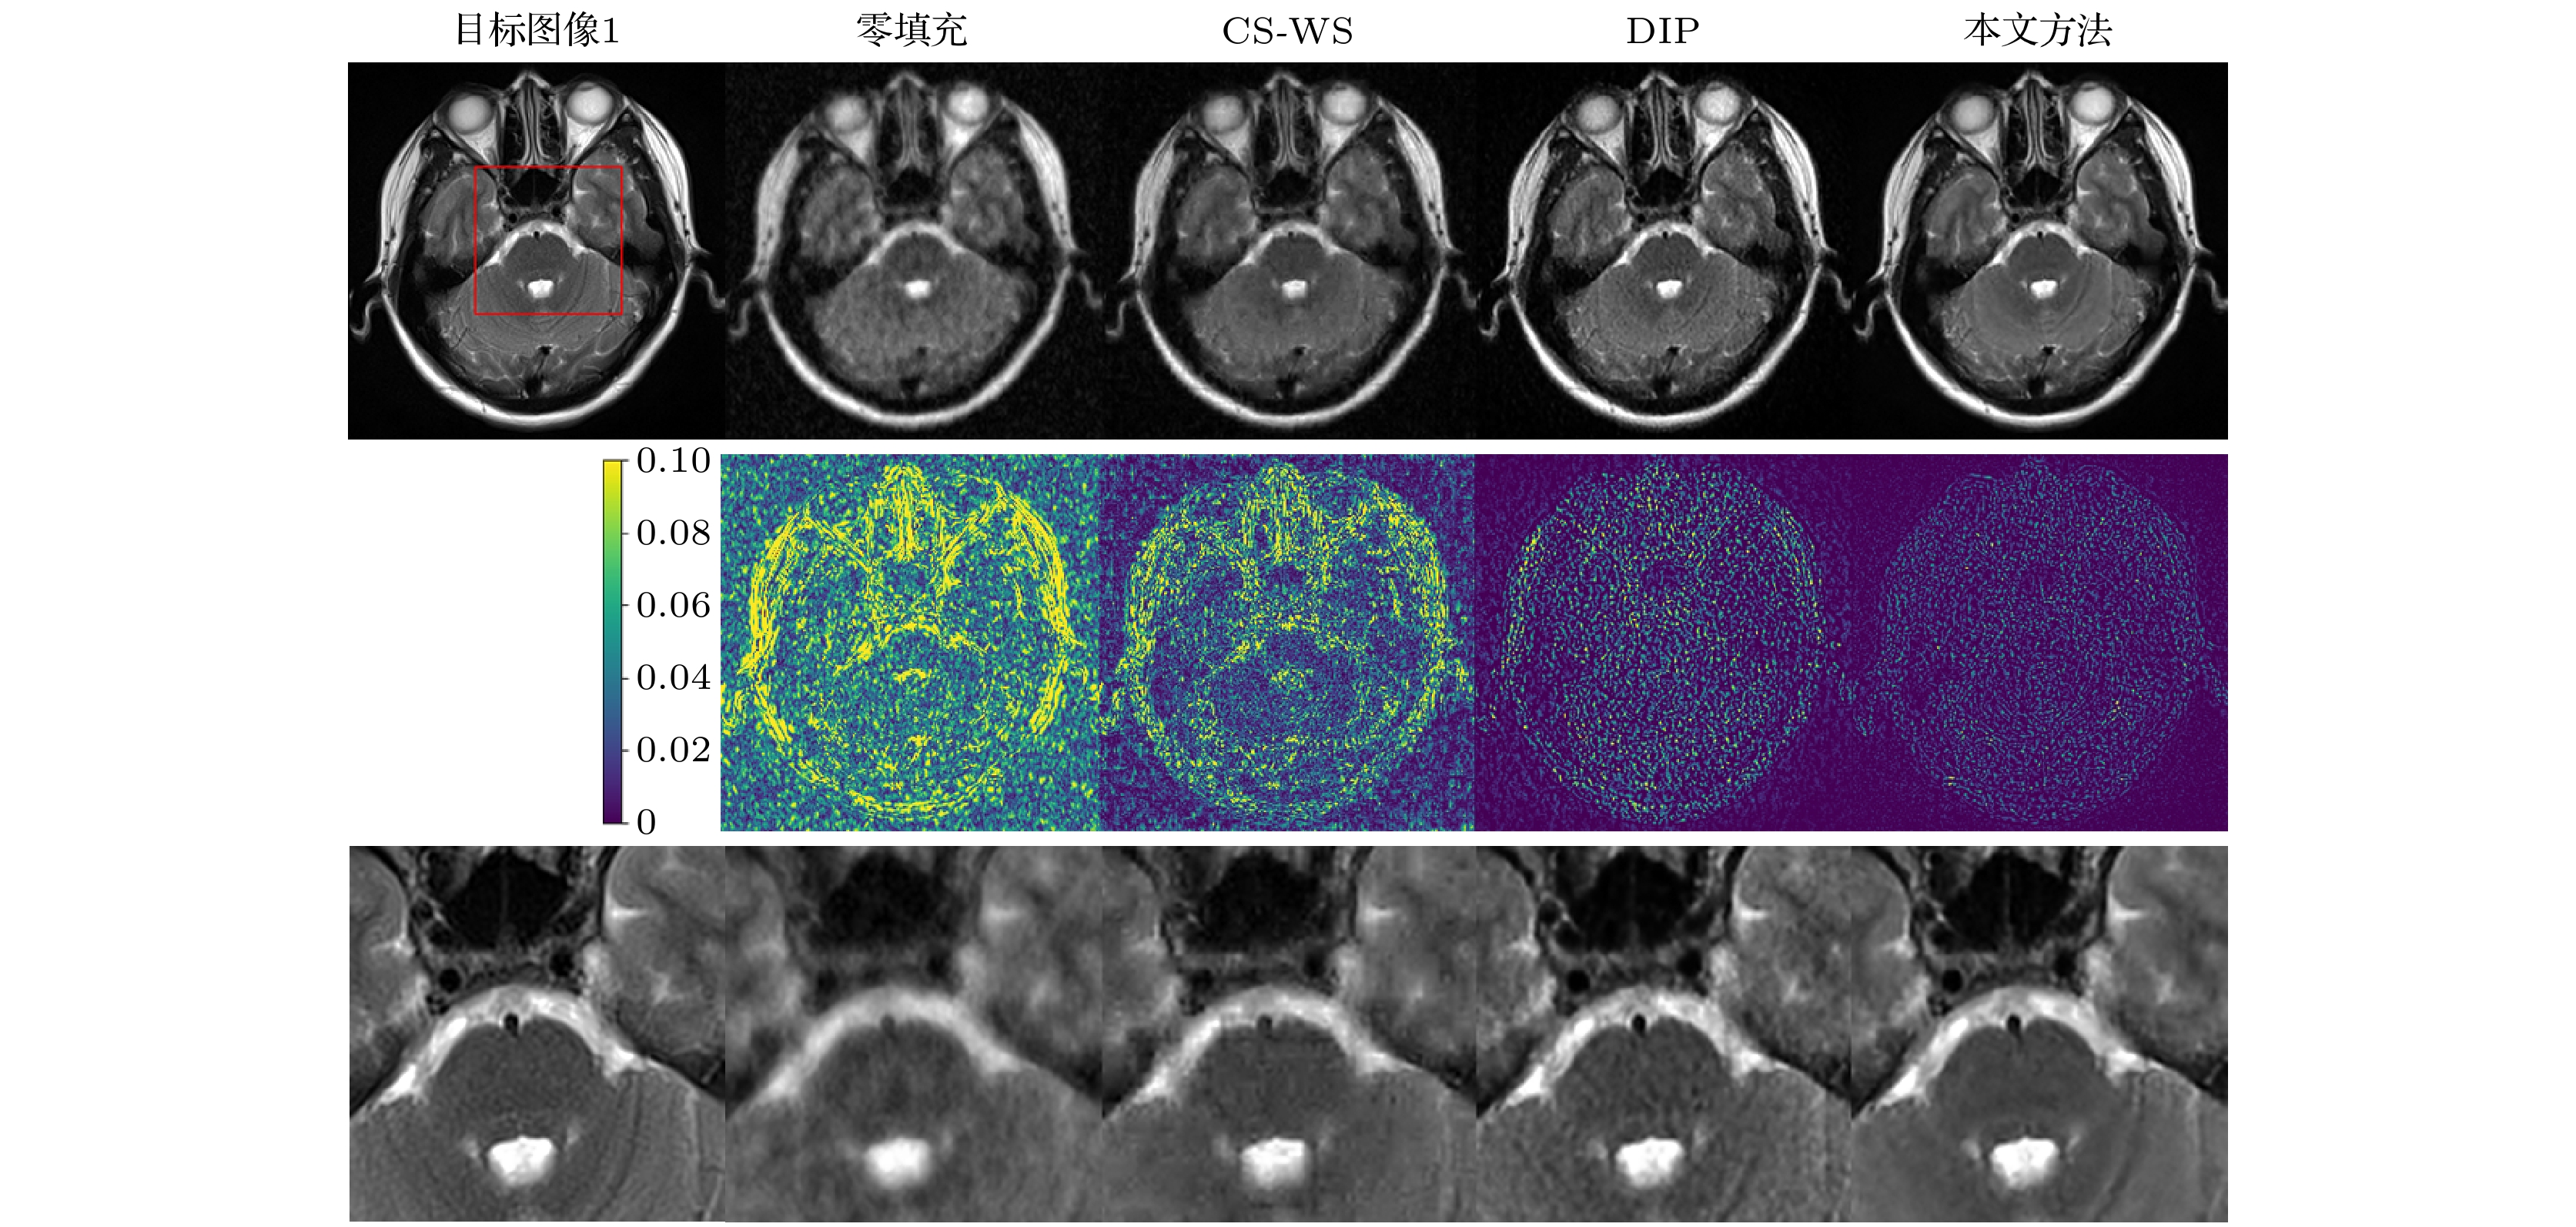

基于深度学习的磁共振成像(magnetic resonance imaging, MRI)方法需要大规模、高质量的病患数据样本集进行预训练. 然而, 由于病患隐私及设备等因素限制, 获取大规模、高质量的磁共振数据集在实际临床应用中面临挑战. 本文提出一种新的基于深度学习的欠采样磁共振图像重建方法, 该方法无需预训练、不依赖训练数据集, 而是充分利用待重建的目标MR图像的结构先验和支撑先验, 并将其引入深度图像先验(deep image prior, DIP)框架, 从而削减对训练数据集的依赖, 提升学习效率. 基于参考图像与目标图像的相似性, 采用高分辨率参考图像作为深度网络输入, 将结构先验信息引入网络; 将参考图像在小波域中幅值大的系数索引集作为目标图像的已知支撑集, 构造正则化约束项, 将网络训练转化为网络参数的最优化求解过程. 实验结果表明, 本文方法可由欠采样 k空间数据重建得到更精确的磁共振图像, 且在保留组织特征、细节纹理方面具有明显优势.Magnetic resonance imaging (MRI) method based on deep learning needs large-quantity and high-quality patient-based datasets for pre-training. However, this is a challenge to the clinical applications because it is difficult to obtain a sufficient quantity of patient-based MR datasets due to the limitation of equipment and patient privacy concerns. In this paper, we propose a novel undersampled MRI reconstruction method based on deep learning. This method does not require any pre-training procedures and does not depend on training datasets. The proposed method is inspired by the traditional deep image prior (DIP) framework, and integrates the structure prior and support prior of the target MR image to improve the efficiency of learning. Based on the similarity between the reference image and the target image, the high-resolution reference image obtained in advance is used as the network input, thereby incorporating the structural prior information into network. By taking the coefficient index set of the reference image with large amplitude in the wavelet domain as the known support of the target image, the regularization constraint term is constructed, and the network training is transformed into the optimization process of network parameters. Experimental results show that the proposed method can obtain more accurate reconstructions from undersampled k-space data, and has obvious advantages in preserving tissue features and detailed texture.

参数 图像 目标图像1 目标图像2 目标图像3 网络超参数 学习率 0.005 0.003 0.003 L 6 6 6 $n_{\rm{d}}$ [32, 64, 64, 64, 128, 128] [16, 32, 64, 64, 128, 128] [16, 32, 64, 64, 128, 128] $n_{\rm{u}}$ [32, 64, 64, 64, 128, 128] [16, 32, 64, 64, 128, 128] [16, 32, 64, 64, 128, 128] $n_{\rm{s}}$ [16, 16, 16, 16, 16, 16] [16, 16, 16, 16, 16, 16] [16, 16, 16, 16, 16, 16] $k_{\rm{d}}$ [3, 3, 3, 3, 3, 3] [3, 3, 3, 3, 3, 3] [3, 3, 3, 3, 3, 3] $k_{\rm{u}}$ [3, 3, 3, 3, 3, 3] [3, 3, 3, 3, 3, 3] [3, 3, 3, 3, 3, 3] $k_{\rm{s}}$ [1, 1, 1, 1, 1, 1] [1, 1, 1, 1, 1, 1] [1, 1, 1, 1, 1, 1] 迭代次数 5000 3000 3000 小波参数 小波函数 Haar Haar Haar 分解层数 7 8 8 P 13500 55000 52000 λ 1 × 10–10 1 × 10–6 1 × 10–9 待重建MR图像 重建方法 10% 20% 相对误差/% PSNR/dB SSIM 相对误差/% PSNR/dB SSIM 目标图像1 零填充 35.64 18.7365 0.5543 16.14 25.6185 0.7135 CS-WS 34.53 19.0101 0.5590 13.74 27.0139 0.7998 DIP 32.51 19.5344 0.6666 12.49 27.8440 0.8989 本文方法 19.89 23.8004 0.8172 9.43 30.2852 0.9793 目标图像2 零填充 19.66 22.5625 0.7550 13.36 25.9204 0.8065 CS-WS 17.14 23.7530 0.7654 10.34 28.1426 0.8507 DIP 15.09 24.9087 0.8473 5.41 33.7814 0.9619 本文方法 7.51 30.9288 0.9454 3.48 37.5915 0.9788 目标图像3 零填充 17.64 23.5716 0.7857 12.76 26.3807 0.8266 CS-WS 15.24 24.8395 0.8139 9.87 28.6144 0.8774 DIP 14.90 25.0660 0.8585 5.43 33.8264 0.9607 本文方法 7.31 31.2228 0.9491 3.53 37.5488 0.9806 待重建MR图像 重建方法 30% 40% 相对误差/% PSNR/dB SSIM 相对误差/% PSNR/dB SSIM 目标图像1 零填充 11.53 28.5361 0.7657 7.71 32.0337 0.8087 CS-WS 9.40 30.3126 0.8689 6.68 33.2736 0.9136 DIP 9.05 30.6386 0.9342 6.98 32.8933 0.9605 本文方法 7.06 32.7970 0.9590 5.64 34.7395 0.9728 目标图像2 零填充 4.61 35.1677 0.8677 3.46 37.6630 0.8830 CS-WS 2.61 40.0883 0.9377 1.95 42.6338 0.9438 DIP 2.80 39.4992 0.9858 2.33 41.1008 0.9892 本文方法 2.08 42.0469 0.9905 1.73 43.6437 0.9931 目标图像3 零填充 4.31 35.8182 0.8813 3.24 38.2961 0.8997 CS-WS 2.45 40.7193 0.9444 1.84 43.1958 0.9601 DIP 3.22 38.5632 0.9824 2.54 40.4324 0.9885 本文方法 2.05 42.2484 0.9908 1.64 44.2051 0.9939 待重建MR图像 采样模板(采样率) 重建方法 相对误差/% PSNR/dB SSIM 目标图像1 径向(20%) 零填充 14.34 26.6426 0.7852 CS-WS 12.11 28.1129 0.8519 DIP 10.95 28.9845 0.9169 本文方法 7.92 31.7960 0.9547 变密度(30%) 零填充 15.03 26.2373 0.7735 CS-WS 11.15 28.8264 0.8662 DIP 9.26 30.4441 0.9321 本文方法 6.43 33.6199 0.9648 目标图像2 径向(10%) 零填充 8.05 30.3202 0.7960 CS-WS 5.73 33.2803 0.9010 DIP 4.40 35.5814 0.9662 本文方法 3.54 37.4434 0.9760 变密度(20%) 零填充 6.47 32.2213 0.8778 CS-WS 3.56 37.4195 0.9625 DIP 3.15 38.4764 0.9821 本文方法 2.57 40.2243 0.9850 目标图像3 径向(10%) 零填充 7.03 31.5576 0.8177 CS-WS 5.18 34.2111 0.9158 DIP 4.73 35.0303 0.9629 本文方法 3.55 37.4852 0.9751 变密度(20%) 零填充 5.82 33.2106 0.8978 CS-WS 3.27 38.2161 0.9675 DIP 3.01 38.9786 0.9819 本文方法 2.54 40.4229 0.9852 采样模板(采样率) 重建方法 相对误差/% PSNR/dB SSIM 径向 (20%) DIP + Ref 8.88 30.9180 0.9478 DIP + Sup 10.35 29.4739 0.9264 DIP + Ref + Sup 8.24 31.5530 0.9512 DIP + Ref + Sup + Cor 7.92 31.7960 0.9547 变密度 (30%) DIP + Ref 7.38 32.4116 0.9583 DIP + Sup 9.08 30.6104 0.9583 DIP + Ref + Sup 6.71 33.2360 0.9620 DIP + Ref + Sup + Cor 6.43 33.6199 0.9648 待重建MR图像 重建方法 计算时间 10% 20% 30% 40% 目标图像1 CS-WS 46 s 46 s 49 s 46 s DIP 2 min 53 s 2 min 43 s 2 min 47 s 2 min 45 s 本文方法 3 min 55 s 3 min 56 s 3 min 54 s 3 min 56 s 图11(d)所示目标图像 CS-WS 42 s 42 s 45 s 44 s DIP 2 min 33 s 2 min 35 s 2 min 35 s 2 min 34 s 本文方法 3 min 14 s 3 min 15 s 3 min 15 s 3 min 13 s -